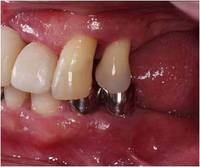

治療前

矢印の部位の骨が、歯根の1/2から2/3にかけて溶けてしまっています。歯肉も炎症を起こしています。